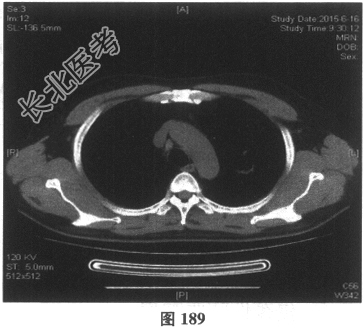

- [材料题] 患者男性,52岁,因间断发热伴咳嗽,咳少许黄痰,无咯血,伴胸闷憋气20余天就诊。体检:体温37.6~38.3℃。既往体健。查体:体温37.6℃,心率83次/分,呼吸20次/分,血压117/64mmHg。神志清,精神可,口唇无发绀;双肺呼吸音粗,可闻及广泛干、湿性啰音,以干啰音为主;心率83次/分,律齐,各瓣膜听诊区未闻及病理性杂音;腹软,无压痛及反跳痛,肠鸣音3次/分,双下肢无水肿。血常规检查:白细胞计数26.32×109/L,中性粒细胞0.846,血红蛋白117g/L,血小板计数1911×109/L;C反应蛋白119.05mg/L。尿常规检查:隐血2(+),蛋白1(+)。痰培养:曲霉菌属,请排除污染。生化全套检查:白蛋白19.6g/L,谷丙转氨酶24.2U/L,谷草转氨酶25.8U/L,γ-谷氨酰基转移酶91.4U/L;尿素氮13.00mmol/L(2.14~7.14mmol/L),肌酐166.8μmol/L(31~132μmol/L);血钾5.6mmol/L。肺部CT见图178~图185。

- 多项选择题4.[提示]患者应用多种抗生素治疗(第三代头孢菌素、青霉素加酶抑制剂)包括抗曲霉菌治疗无效,加用甲泼尼龙40mg静脉滴注病情好转。肺部CT检查显示病变明显改善。尿常规检查正常, 肾功能检测正常。复查肺部CT(图188~图195):示病变较前好转。Wegener肉芽肿的主要临床表现是( )